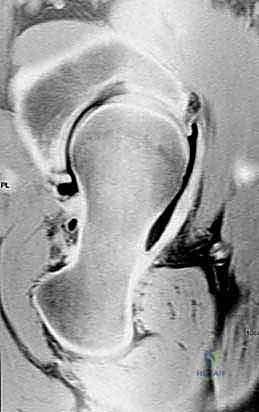

- النخر اللاوعائي لرأس الفخذ (Avascular Necrosis - AVN): في المراحل المبكرة قبل انهيار رأس الفخذ، يمكن تغيير زاوية العظم لإبعاد المنطقة الميتة عن منطقة تحمل الوزن الأساسية، وإحلال منطقة غضروفية سليمة مكانها.

- التصوير الشعاعي المتقدم: استخدام الأشعة السينية بوضعيات محددة، والأشعة المقطعية (CT Scan) ثلاثية الأبعاد، والرنين المغناطيسي (MRI) لتقييم حالة الغضروف بدقة.

هنا يأتي دور الجراحة التقويمية التي يجريها الأستاذ الدكتور محمد هطيف؛ حيث يتم إجراء قطع عظمي دقيق في المنطقة الواقعة بين المدور الأكبر والمدور الأصغر (Intertrochanteric Region)، وهي منطقة تتميز بتروية دموية ممتازة مما يضمن التئاماً سريعاً للعظم. بعد القطع، يتم تعديل الزاوية لتوزيع الأحمال بشكل متساوٍ على مساحة أكبر من الغضروف السليم، مما يوقف أو يبطئ بشكل كبير عملية التآكل.